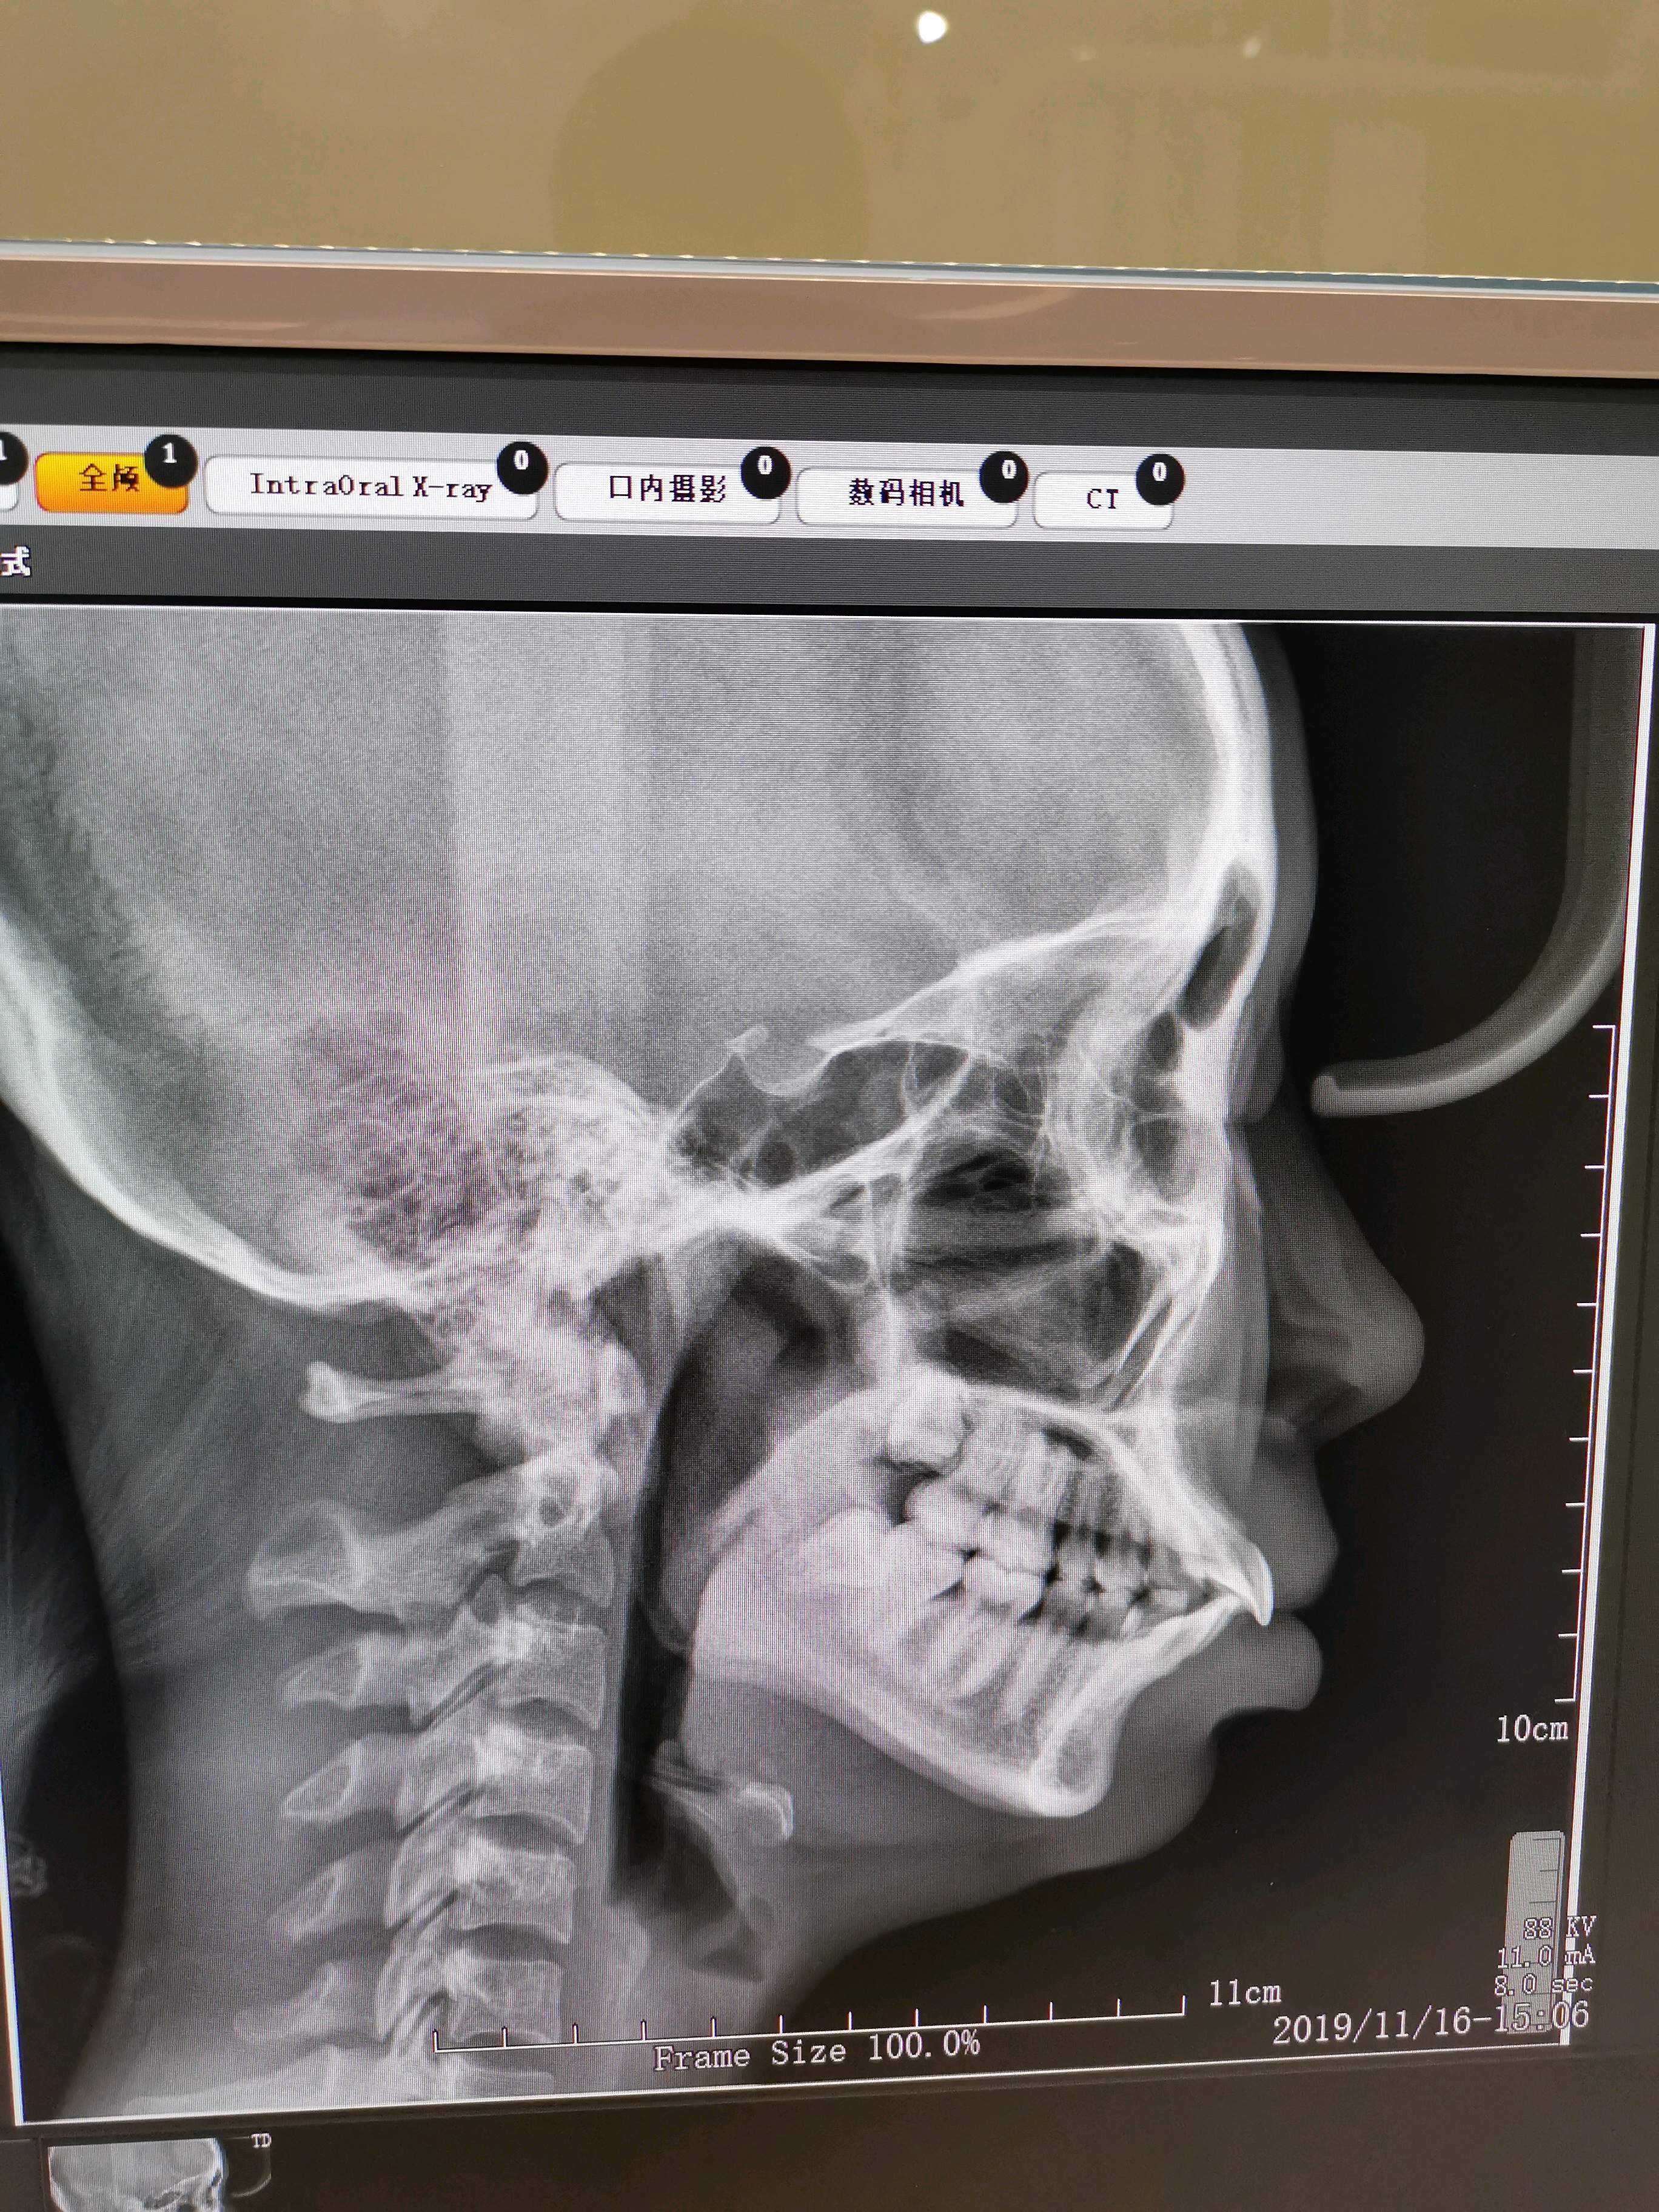

你好我这是骨性凸嘴还是齿性凸嘴以为不严重没想到凸嘴一点气质都没有

嘴突有辣么多种看看你是哪一型之骨性前突

不过嘴凸又有三种情况:一种是骨性造成的,也就是上颌骨突出;还有一种